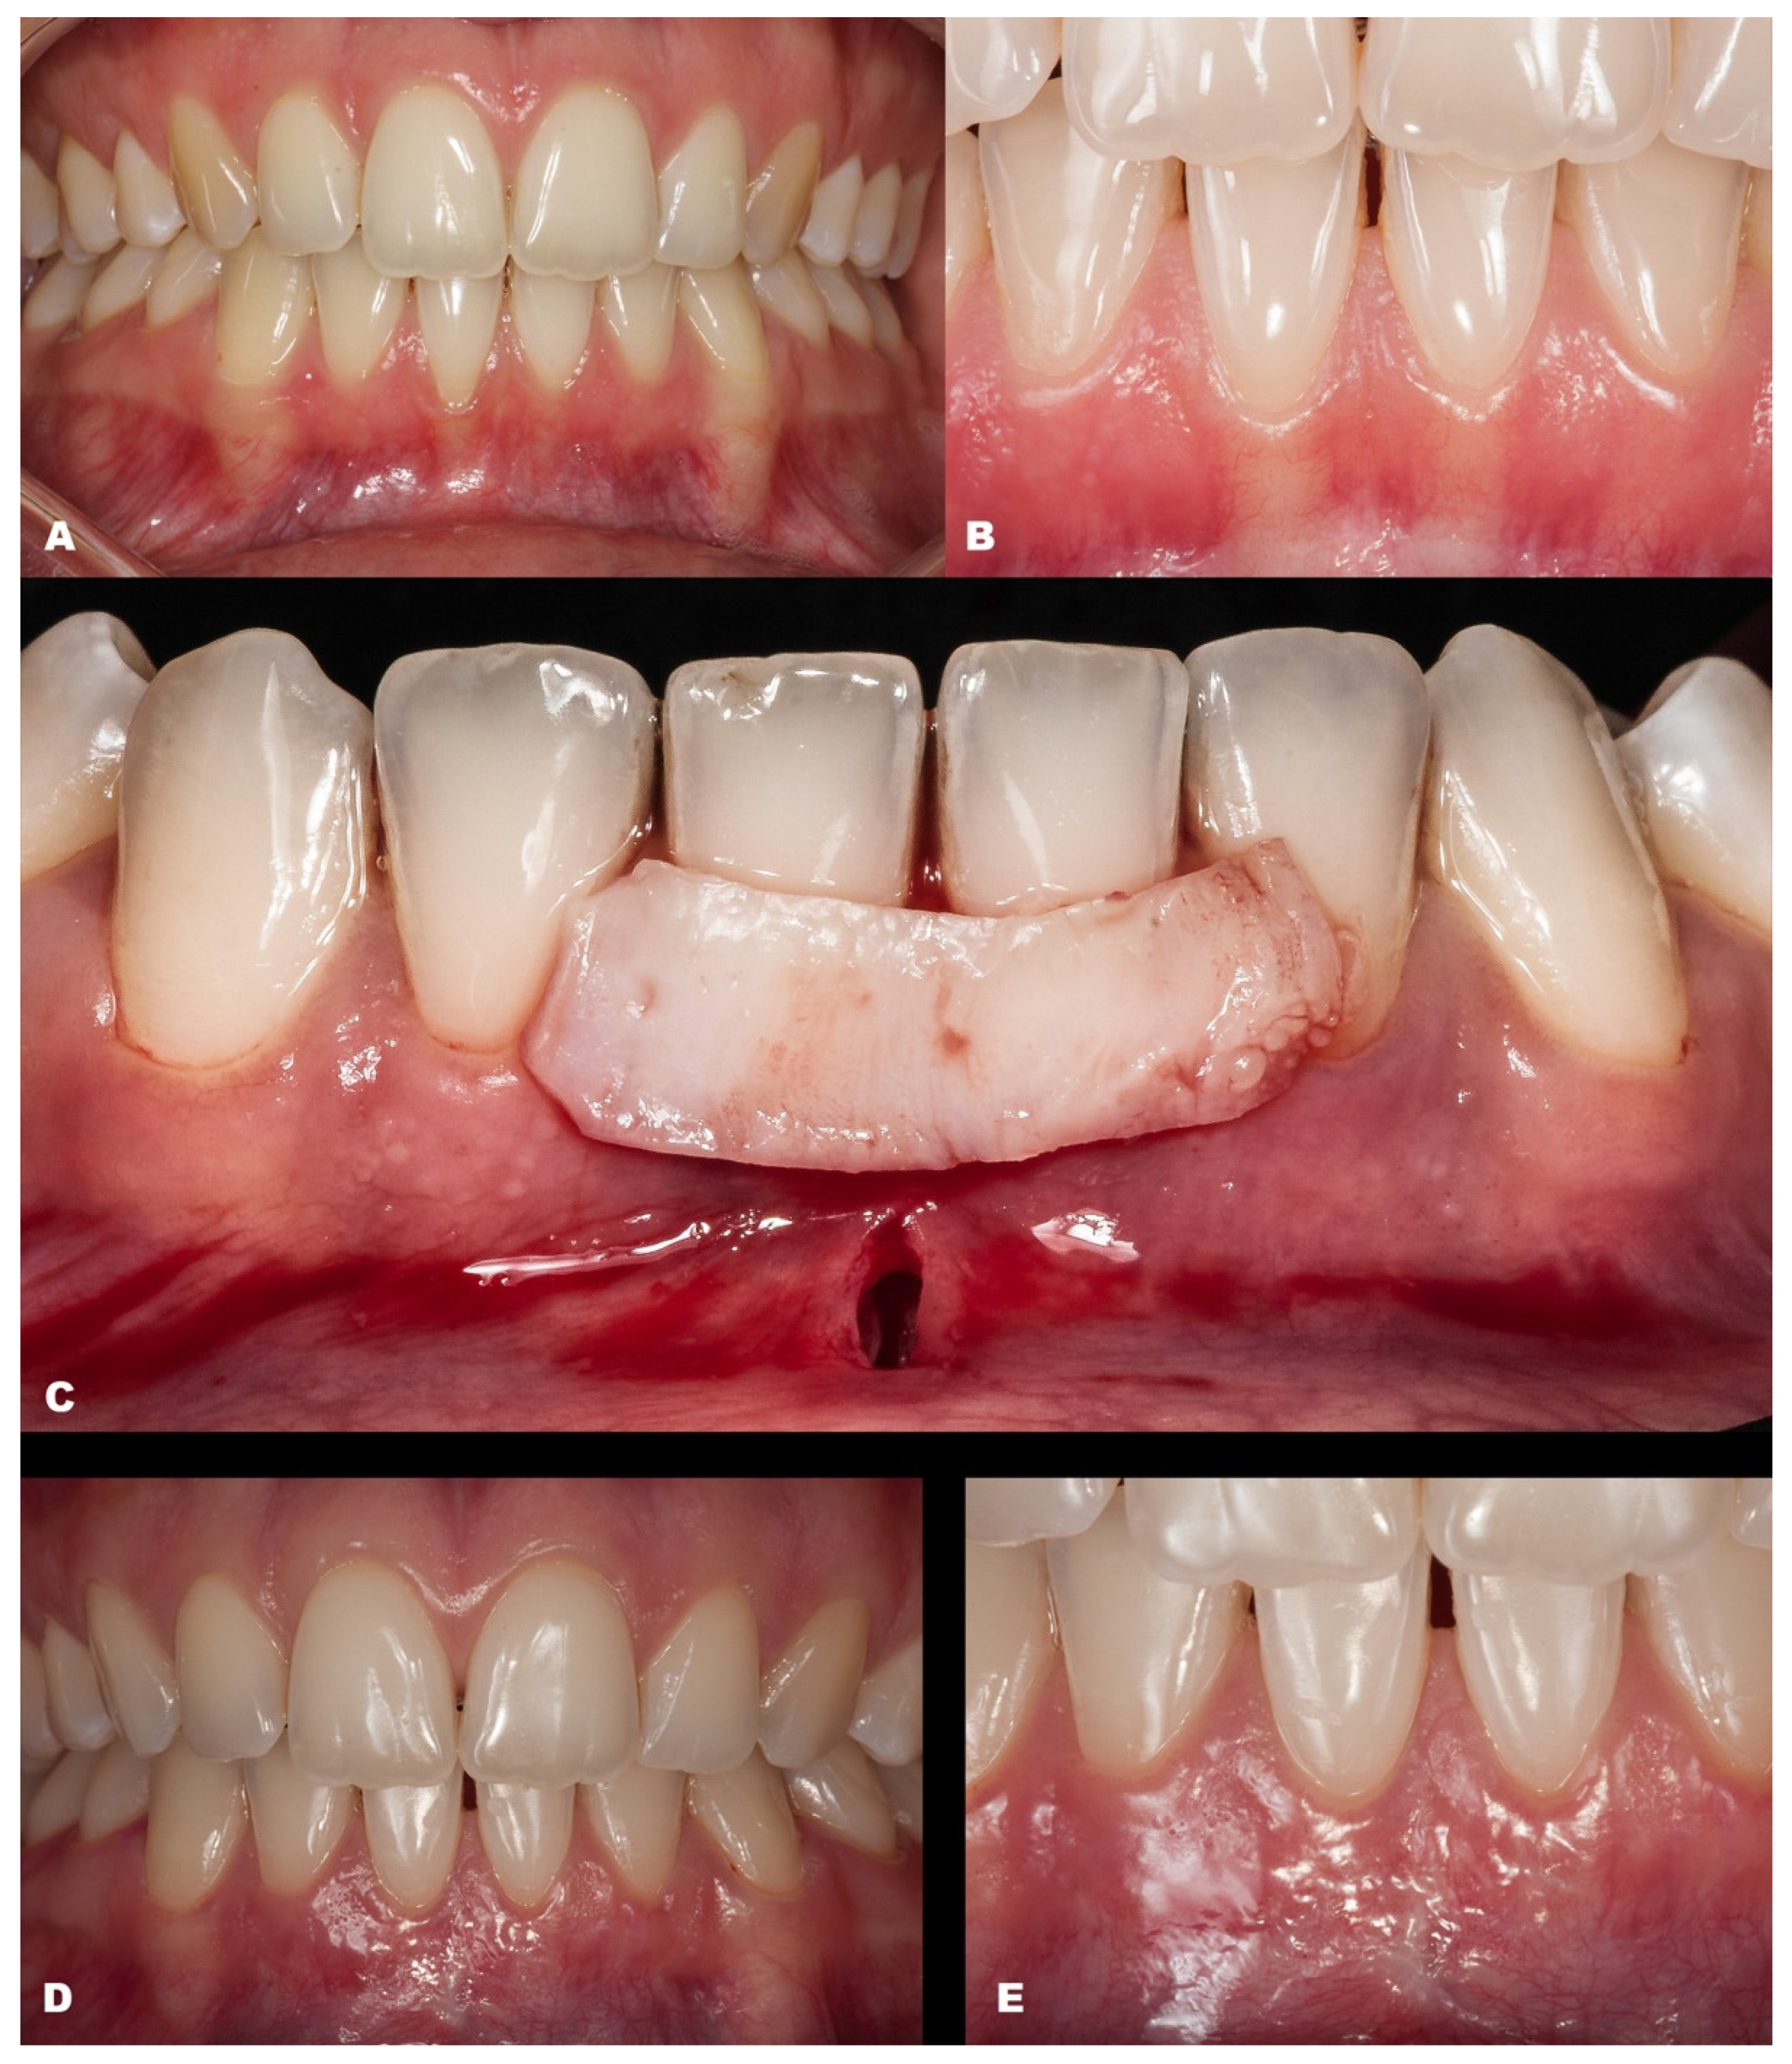

- After CTG is harvested (either subepithelial or de-epithelialized), it will be inserted in the desired site through the linear incision or intrasulcularly (Figure 1K,L).

- (7)

- The CTG will be adjusted to cover the recession (Figure 1l) and must be coronally advanced at least 1 mm coronal to the CEJ.

- (8)

- Then, MiTT should be sutured according to the personally preferred technique. It is suggested that the suture techniques slightly pull the tunnel coronal (anchored with composite or double-crossed suture [18]). The vertical incision must be sutured with one or two single sutures. It is suggested to stabilize the soft tissues using interrupted sutures, and it may be used as adjunctive material, such as a biological glue. It is suggested that the suture be removed between 7 and 14 days.

| Classification | Gender | Tooth/Teeth with REC | Initial REC Height (mm) | Initial REC Width (mm) | Initial PD (mm) | Initial KTW (mm) | Final REC Height (mm) | Final PD (mm) | Final KTW (mm) | % RC | p-Value | |

|---|---|---|---|---|---|---|---|---|---|---|---|---|

| Baseline | 6-Month Follow-up | |||||||||||

| Case 7 | RT1 | F | 12 11 21 22 | 1.1 1.5 2.4 1.5 | 1.5 3.0 4.0 2.0 | 1.0 2.0 1.5 2.0 | 5.4 5.0 6.3 6.9 | none | 1.0 2.5 2.5 1.5 | 4.3 5.7 6.0 6.3 | 100 100 100 100 | |

| Case 8 | RT2 | F | 42 41 31 32 | 2.2 3.4 3.2 1.2 | 2.3 2.5 3.0 2.7 | 0.5 0.5 0.5 1.0 | 2.4 1.9 1.5 3.5 | 0 0.6 0.6 0.5 | 1.5 1.0 1.0 1.0 | 3.6 2.9 2.1 3.3 | 100 82.35 81.25 58.34 | |